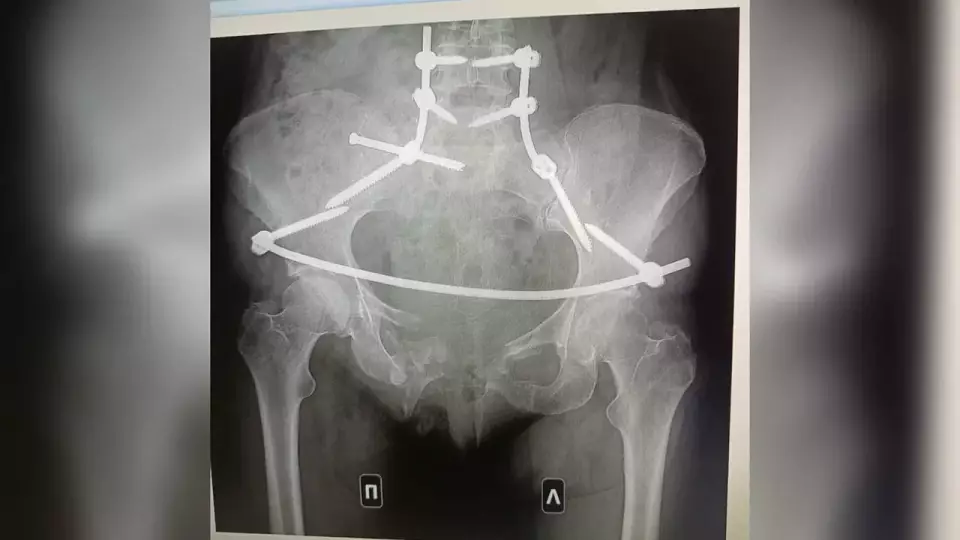

В тот роковой вечер сосед Дмитрий Д., будучи пьяным, сел за руль и начал угрожать соседям. Когда Ирина и Антон попросили его убавить музыку, Дмитрий наехал на них на машине, серьезно ранив Ирину. Женщина перенесла множество операций и до сих пор находится на восстановлении. Ее муж отказался от своей жизни, чтобы ухаживать за ней. После долгой борьбы суд приговорил Дмитрия к 14,5 годам тюрьмы, но по слухам, он мог подписать контракт и уйти на СВО, пишет МегаТюмень.